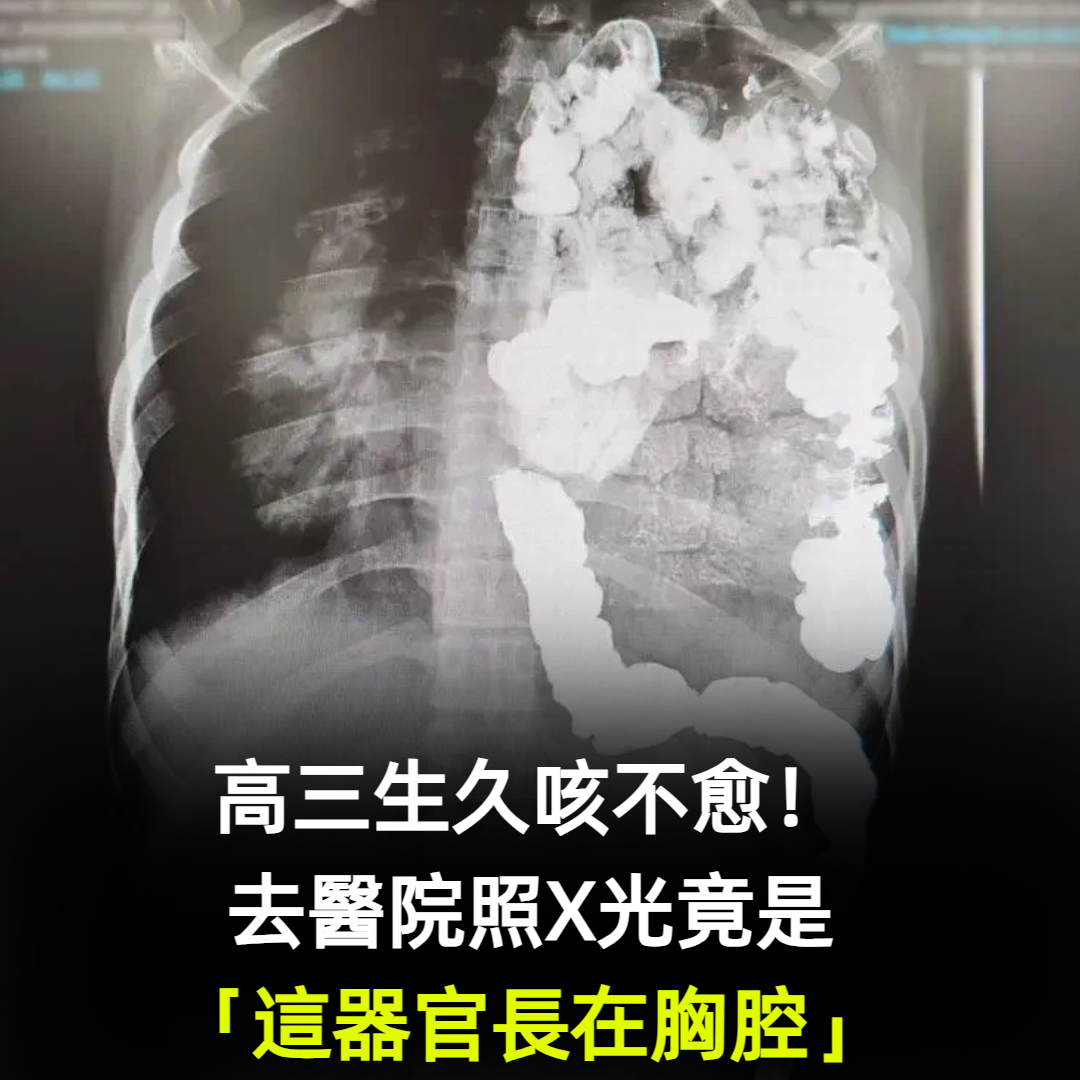

高三生久咳不愈!去醫院照X光竟是「這器官長在胸腔」

嚴重的先天性膈疝會引起新生兒肺發育不良,出生后出現呼吸窘迫、缺氧表現,也是導致新生兒呼吸窘迫甚至新生兒死亡的重要原因之一,男孩媽媽更說,此前,男孩一直沒有表現出其他異常,17歲的他身高超過一米七,體重也超過了70公斤,就是容易感冒,跑跳以後很容易喘不上氣,「初二的時候體檢查出了膈疝,但是當時醫院說做手術風險大,加上孩子沒有癥狀,就一直沒太重視。」。